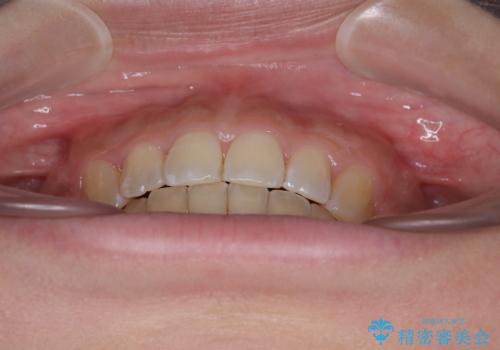

八重歯と上顎前突 ワイヤー装置での抜歯矯正

上下の前歯が接触する仕上がりとなったので、横顔の印象が大幅に改善されました。